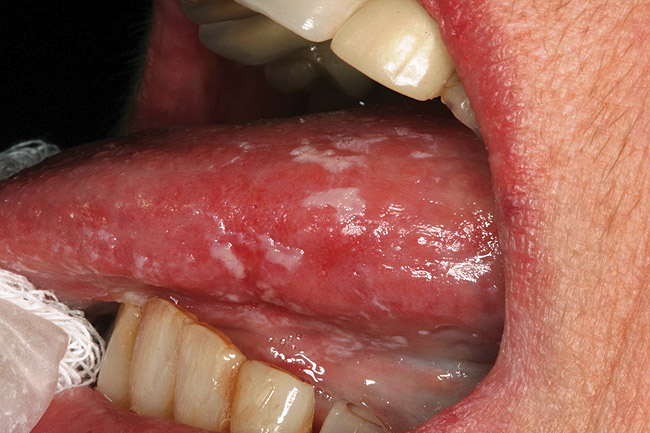

Saliva aids for oral cavity cleansing, swallowing, taste, speech, and digestion could be compromised in patients with salivary gland hypofunction. The oral mucosa may appear dry and friable. The tongue may appear dry and fissured (Figure 1). Dental caries, plaque accumulation, gingivitis, and periodontitis are common in patients with significant salivary gland hypofunction (Figure 2). Infections, such as oral candidiasis (Figure 3), and enlargement of salivary glands from sialadenitis are seen commonly in patients with moderate-to-severe salivary gland hypofunction (Figure 4). Difficulty in mastication and swallowing also may indicate advanced salivary gland hypofunction19 and can contribute to poor nutrition.20 Denture retention may become difficult because of the lack of saliva12 (Table 3).

Figure 1  Tongue appears dry and fissured in a patient with salivary gland hypofunction.

Figure 1

Figure 3  Oral candidiasis (pseudomembranous) is seen as elevated white plaques on the dorsal and lateral surfaces of the tongue.

Figure 3